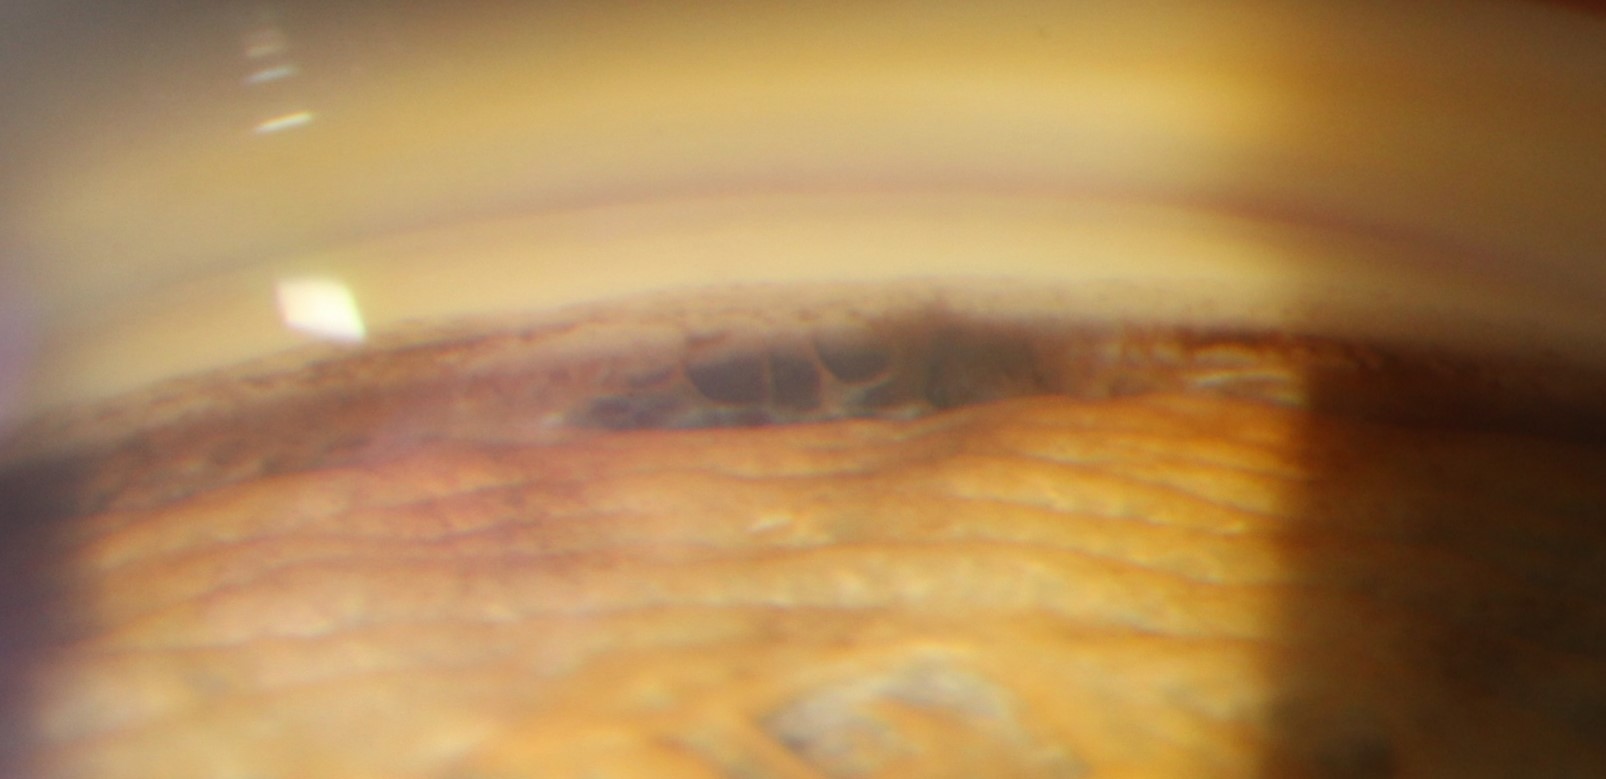

Secondary open angle glaucoma occurs as a result of a separate condition that results in cells, pigment, blood or other debris obstructing aqueous outflow. Conditions that may potentially cause secondary open angle glaucoma include pigment dispersion syndrome, pseudoexfoliation syndrome, hyphaema (trauma) and steroid-induced glaucoma.

Secondary angle closure glaucoma occurs when the angle is obstructed by iris and/or angle changes, or by a forward movement of the crystalline lens, causing a mechanical obstruction of aqueous drainage termed pupillary block. The most common cause of secondary angle closure glaucoma, particularly in developing countries, is a hyper-mature cataract which causes the lens to move forward, obstructing aqueous outflow.